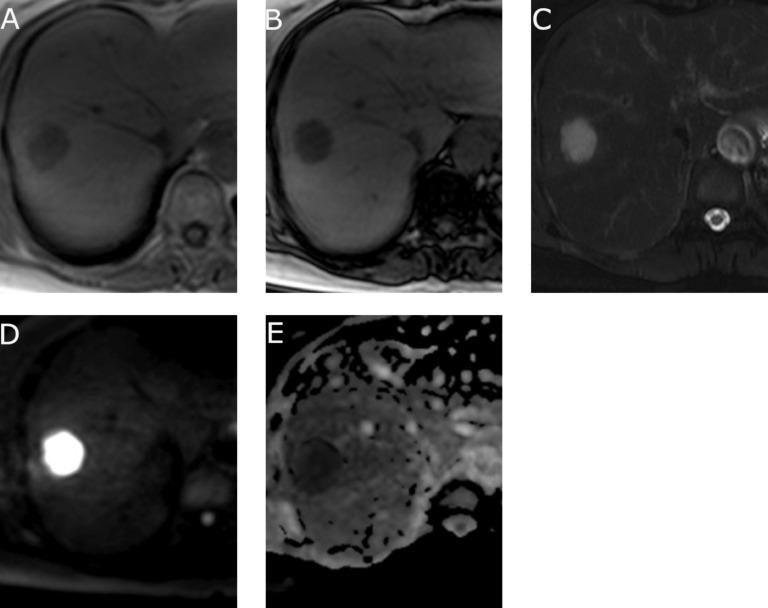

A case of primary clear cell hepatocellular carcinoma comprised mostly of clear cells.

Clear cell hepatocellular carcinoma (CHCC) is defined as a tumor which contains more than 50% of clear cells. However, CHCC with more than 90% of clear cells are extremely rare. We report a case of a 65-year-old woman who was found to have a solitary mass, which was histologically diagnosed as clear cell hepatocellular carcinoma composed of 90% or more clear cells. The tumor presented rim arterial phase hyperenhancement in computed tomography, magnetic resonance imaging, and computed tomography during hepatic arteriography, and was classified as LR-M category according to The Liver Imaging Reporting and Data System version 2018(LI-RADS v2018). This tumor may mimic other tumors with similar radiographic features, such as intrahepatic cholangiocellular carcinoma and metastatic tumor.